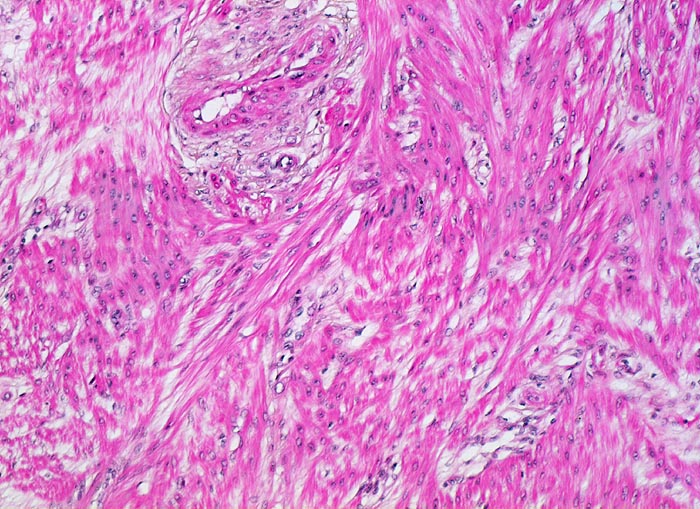

Gravidität: Myometrium

Normalbefund

Hyperplastisches Myometrium mit grossen Myozyten und aufgelockertem Interstitium.

11. Schwangerschaftswoche. Normale Schwangerschaft

Histologie

100